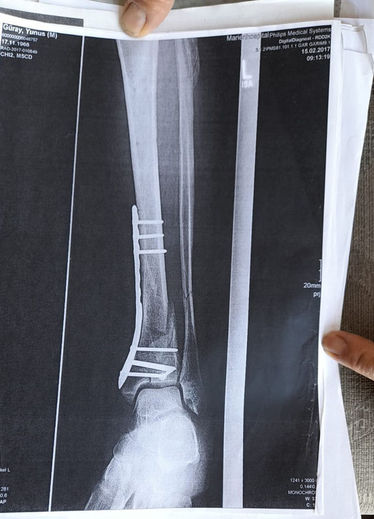

"AYAĞIMDA DEMİR VAR, SAKAT BIRAKTILAR"Olay yeriyle ilgili fotoğraf ve görüntüleri mahkemeye sunduklarını kaydeden Güray, "Ömrümü yediler, demir var ayağımda, sakat bıraktılar. Ayağı keseceklerdi neredeyse. Şu an kalıcı sakatlık var. 1 sene kendime gelemedim, 2 haftada bir ameliyata giriyordum. Almanya'da 3 ay hastanede kaldım ve ayağımda yüzde 3'lük engel oluştu" diye konuştu.

"O ÇUKURLARI 3 AY SONRA KAPATTILAR"Tazminat miktarını düşük bulan Yunus Güray, şunları söyledi: "Benim uçak masrafım sadece 22 bin avro tuttu. 9 yıl oldu, bir tane çukur değildi. Adamlar kazmış, kazmış, bırakmış. Tam merkezde bu olay, hani ormanda bir yerde olur, 'Tamam benim de hatam var. Gittim de düştüm' derim. Ama şehrin merkezinde, etrafı çevrili değildi. Yemyeşil alan, gece vaktiydi. Ben mahkemeye verdim, o çukurları 3 ay sonra kapattılar. 6- 7 yerde kazılmış çukurlar vardı. Bir tane değildi. Ayağımda hala demir var. Adil bir karar olmadı."